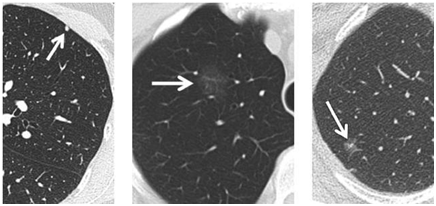

根据肺结节的密度分为:纯磨玻璃结节、实性结节、部分实性结节。

从左至右分别是实性结节、纯磨玻璃结节、部分实性结节